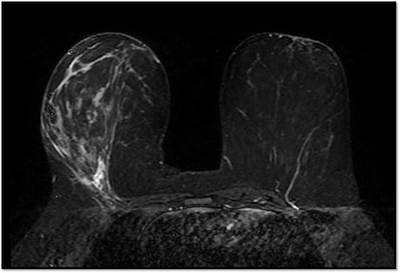

MG: Right breast shows focal asymmetric density in lateral quadrant extending for an area of 12.4 x 6.5 cm with no associated discrete mass or suspicious calcifications. Correlative ultrasound showed a heterogeneous area with echogenic vascular surrounding parenchyma in lateral quadrant with no discrete solid masses. MRI breast was performed on day 14 of LMP. Right breast shows an area predominantly consisting of fat in lateral quadrant extending for an area of 1.2×5.5x 8.9 cm along its maximum AP, ML and CC dimensions. This area is bright on fat suppressed T2 sequences and shows significant restriction on diffusion weighted sequences. There is rapid and progressive non mass enhancement in the above area extending anteriorly in to the nipple and posteriorly into the pectoralis major muscle. Two large and tortuous feeding vessels are seen to arise from the subclavian and axillary arteries respectively. Right breast shows predominantly fat containing mass showing abnormal enhancement described. The possibilities include vascular neoplasm or remotely fat necrosis. Ultrasound guided core biopsy was Suggestive of an inflammatory lesion, possibly fat necrosis. However enlarged and tortuous feeding arteries to the vascular mass was worrisome and we recommended an excision biopsy correlation. Excision biopsy showed “Multiple patchy areas of dense inflammatory infiltration in a background of fat necrosis”.